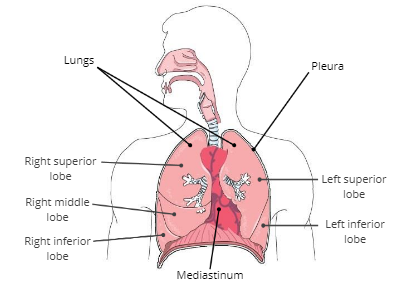

Lungs

soft, spongy organs in the thoracic cavity that are responsible for gas exchange

Mediastinum

a compartment in the center of the thoracic cavity that contains the heart, trachea, and esophagus.

Pleura

a thin, double membrane that surrounds each lung and lines inner surfaces of the thoracic cavity

Pleural fluid

fluid in between the pleura that reduces friction during breathing